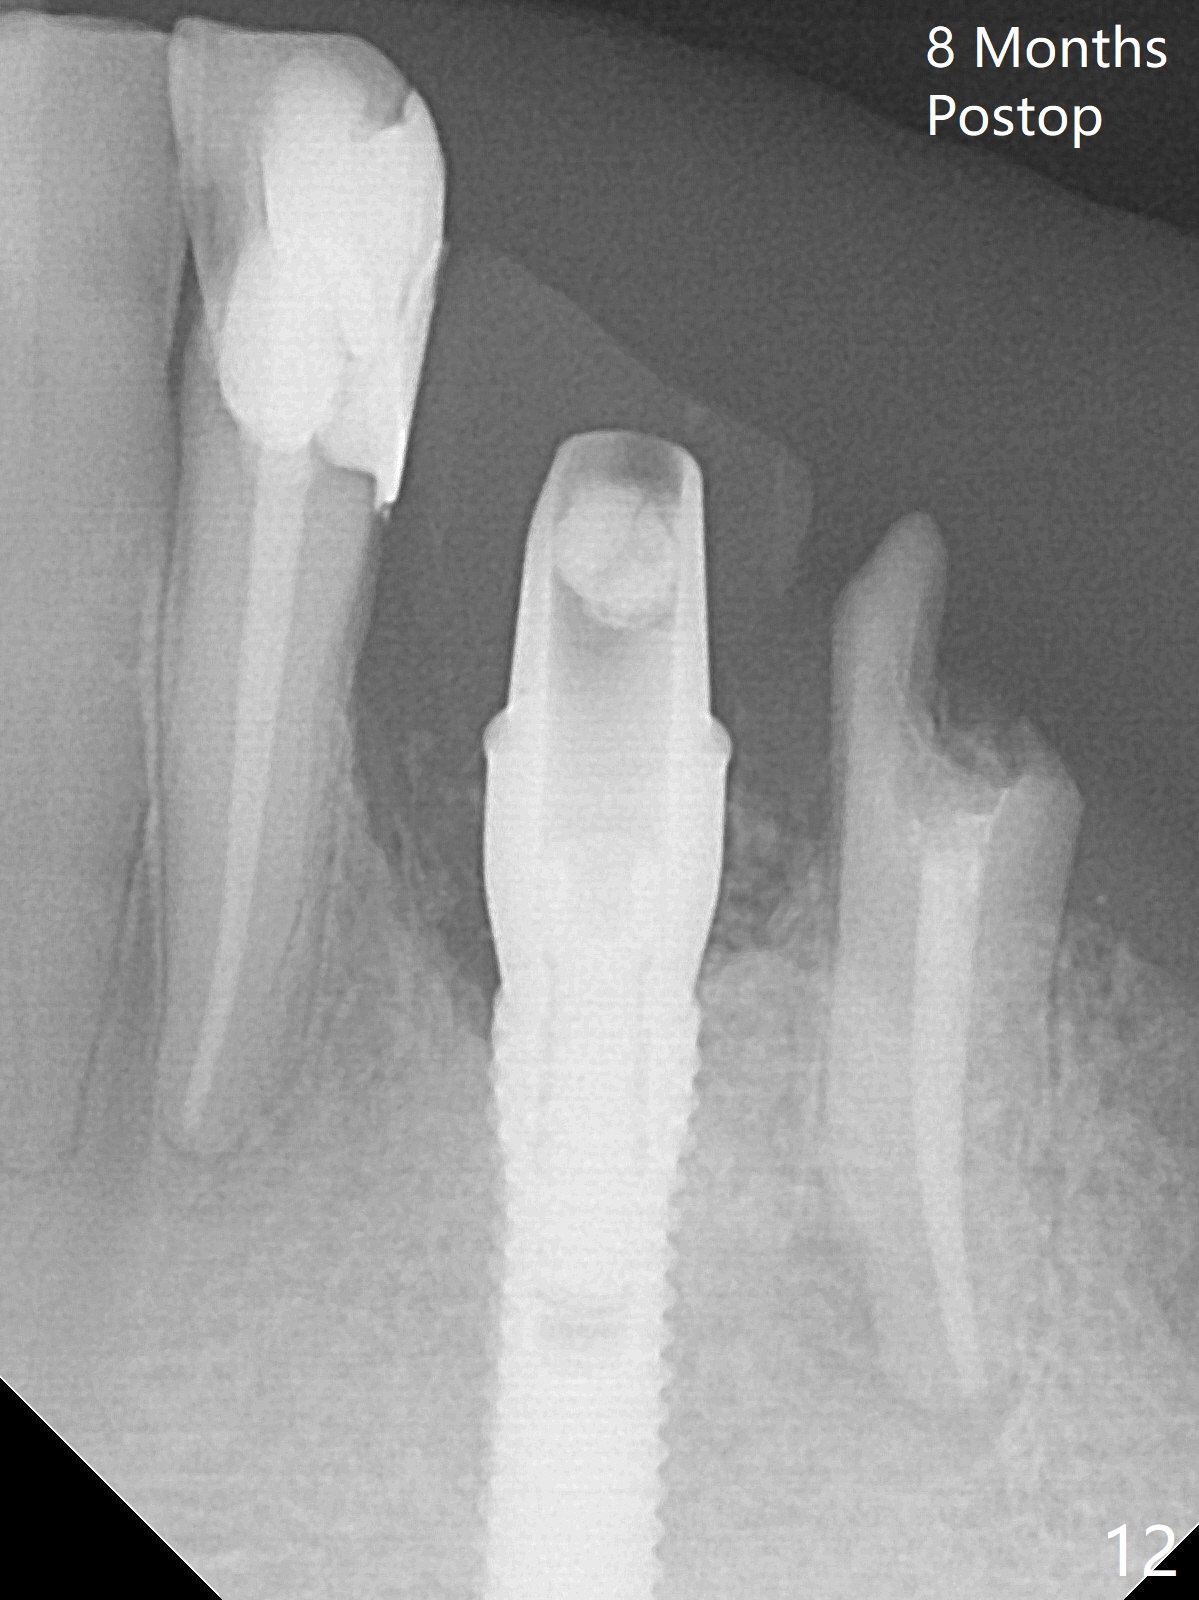

After removal of the split residual roots at #22 (Fig.1), the buccal wall is found to be defective, while the coronal portion of the lingual one (Fig.2 L) is confirmed to be more buccal than the apical portion. A vertical slot is made in the coronal portion of the lingual plate (Fig.3 *) in order to establish osteotomy lingual (Fig.4 O). The depth of the osteotomy in the apical native bone is 4.8 mm (Fig.5 CT coronal section). After the final drill (3 mm) is removed, a 3.8x16 mm implant is placed lingually for secure 2-pointed fixation (Fig.6,7, coronally: mesiolinguodistal; apically: in the native bone (Fig.9)). The essence of the lingual placement is the presence of a large buccal gap for Osteogen plug (Fig.8 yellow) and allograft (Fig.8 red, 9,10 (*)) for potential regeneration of the buccal plate. With bone graft and the overlying provisional (Fig.11 P), the buccal plate seems to have been established (*) 1 week postop. There is no obvious implant thread exposure 8 months postop (Fig.12). But the buccal plate is atrophic when the crown is cemented (~10 months postop, Fig.13).